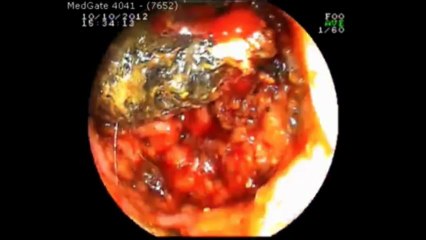

Prof Dr Kayıhan Günay polip çıkarılması.